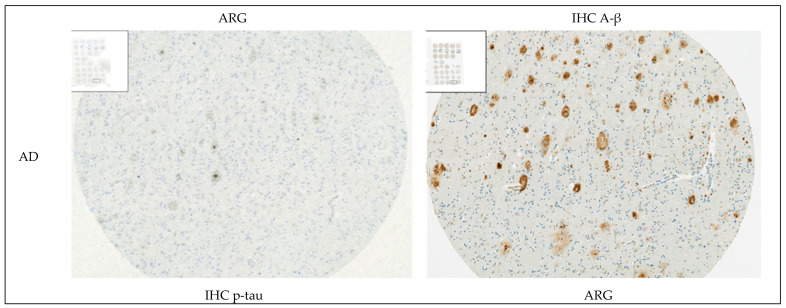

In synucleinopathies (PD and MSA), cerebral amyloid angiopathy (CAA), AD, and 4R tauopathies (PSP and CBD), the specific binding of 25 nM [3H]GMC-058 was significantly higher than the displaceable binding in controls (p < 0.01, ANOVA with Dunnett’s multiple comparisons test; see Table 4 and Figure A6). High-resolution autoradiography showed that the binding of 25 nM [3H]GMC-058 co-localized with α-syn inclusions in PD and MSA, with dense Aβ plaques in CAA and AD, and with p-tau inclusions in PSP and CBD (Figure 4, Figure A7, Figure A8 and Figure A9).

We then conducted autoradiography experiments in fresh-frozen tissue for which α-syn, Aβ, and p-tau expression was measured via IHC. We selected tissue sections of cerebellum from two donors with MSA, of superior frontal gyrus from one donor with CBD, of globus pallidus (GP) from two donors with PSP, and of the cingulate cortex, caudate, GP, and putamen from two controls (Figure 5 and Figure A10 and Table A8).